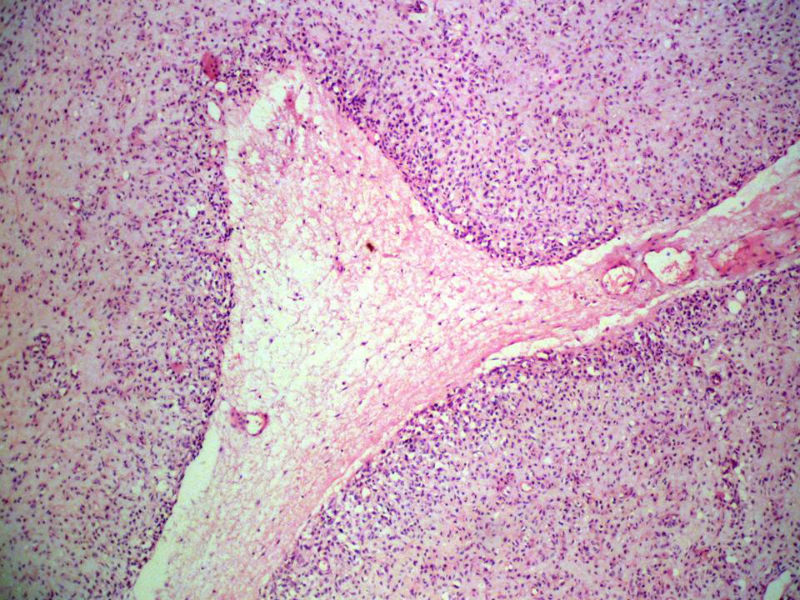

男,27岁,右股骨上段皮下肿物1年余,无明显疼痛,检查肿物明显隆起于皮下,边界清楚,手术完整切除肿物。肉眼,肿物6X6X5厘米,外观多结节状,似有包膜,切面灰白色,质韧。

特别提示:镜下核分裂3-4/HP.

3. 本例组织学改变与粘液性脂肪肉瘤,粘液样纤维肉瘤,纤维粘液样肉瘤,骨外粘液样软骨肉瘤都有重叠之处,且镜下并未见典型结构。由此,免疫组化结果就尤显重要。特别是专业书籍提到,突触素或嗜铬素阳性,对鉴别诊断有重要意义。我用CGA,也是在以上几个肿瘤中举棋不定而为。NSE和CK没用,其实我想用更多的抗体来证实更多的东西,但患者的经济条件不太好,遗憾!